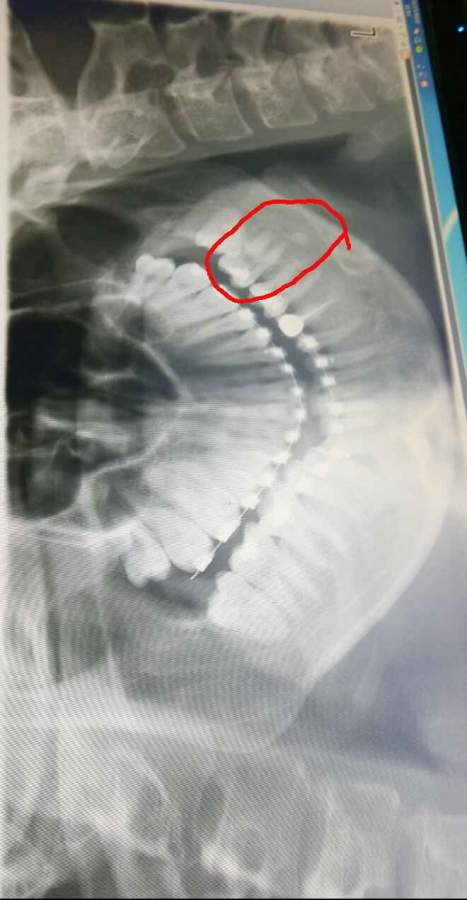

请问谁知道?牙齿下面的一块白的是什么?拍了好多次照片,每次都有。 发自小木虫Android客户端 |